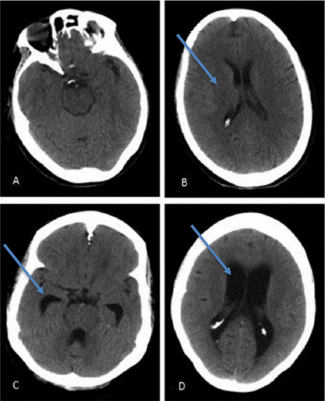

Dysfunction with secretion, circulation or reabsorption of CSF, and its subsequent build-up, could lead to presenting symptomatology of primary idiopathic NPH known as the Hakim-Adams triad [11]. The Hakim-Adams triad typically presents with gait abnormalities first. Nevertheless, like was seen in our patient case, gait can be difficult to gauge due to the patient’s medical history or ambulatory status. Gait abnormalities manifest as the CSF accumulation applied pressure to medial somatomotor pathways of the lower extremities [11,18,19]. Cognitive impairment soon manifests as the build-up of CSF impacts the anterior aspects of the brain via enlargement of the anterior horn of the lateral ventricle, leading to multiple mental impairments (Figure 1) [19]. As accumulation of CSF continues, the pressure on cerebral capillaries leads to ischemic damage, resulting in Dementia [11]. Other cognitive impairments include emotional lability, apathy, and mood dysregulation due to subcortical damage [6]. Finally, incontinence and nocturia set in as pressure upon thalamic projections accrue, completing the triad.

Figure 1: A and B: CT Scan of 71-year old female presenting with normal cognitive function with normal ventricular size whereas C and D are a CT scan of that of a 68-year old female with NPH with visible enlarged ventricles [14].